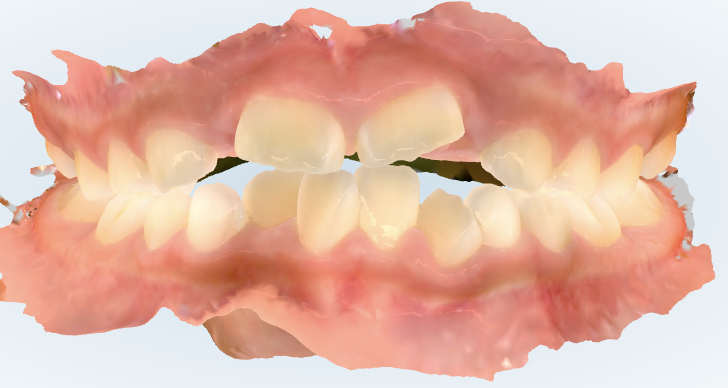

初診時の画像診断

上下の歯並びがガタガタしています。

上の前から2番目の大人の歯がまだ生えていません。

わかりました。妹さんも上下の歯並びにガタガタがあります。上の歯並びはガタガタが少ないように見えますが、前から2番目の歯がこれから隙間に生えてくるため、今後ガタガタになることが予想されます。